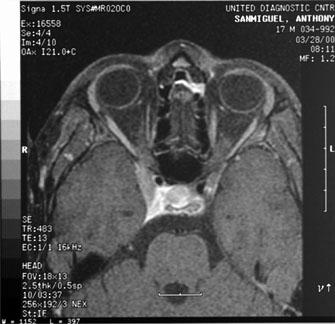

Optic nerve hypoplasia, unless subtle, usually is diagnosed on fundus examination. Although most cases are idiopathic, maternal gestational diabetes and use of phenytoin are well-known risk factors; more recent epidemiologic studies have also suggested that young maternal age, first parity, smoking, and use of fertility and antidepressant drugs may also play a role.27 If bilateral, this condition may be associated with congenital nystagmus. De Morsier's syndrome (septo-optic dysplasia) refers to the constellation of bilateral optic nerve hypoplasia, absence of the septum pellucidum (Fig. 5), thinning or absence of the corpus callosum, dysplasia of the anterior third ventricle, and pituitary dysfunction (see Chapter 5, Fig. 9). Brodsky and Glasier28 broadened the spectrum of this condition. In a study of 40 children, some optic nerve anomalies were isolated, but in other children, midline craniofacial defects, hemispheric gray matter dystrophic anomalies, and posterior pituitary ectopia were noted. Of 21 cases of optic nerve hypoplasia described by Zeki et al,29 there were midline central nervous system defects in six and endocrine deficiencies in nine. In the series of 35 patients with bilateral optic nerve hypoplasia described by Siatkowski et alet al30 neuroradiographic abnormalities were seen in 46% and endocrinopathies in 27%. Growth hormone deficiency was the most common endocrine abnormality. The visual spectrum ranged from 20/20 in one case to no light perception in 34% of patients; 80% were legally blind (20/200 or less in both eyes). Absence of the septum pellucidum and corpus callosum, with panhypopituitarism, occurred in only 11.5% of all patients with bilateral optic nerve hypoplasia. Recently, a sporadic mutation in the HESX1 gene has been reported to cause optic nerve hypoplasia with pituitary insufficiency.31

Fig. 5. Magnetic resonance image of patient with bilateral optic nerve hypoplasia demonstrating absence of septum pellucidum with single midline ventricle.